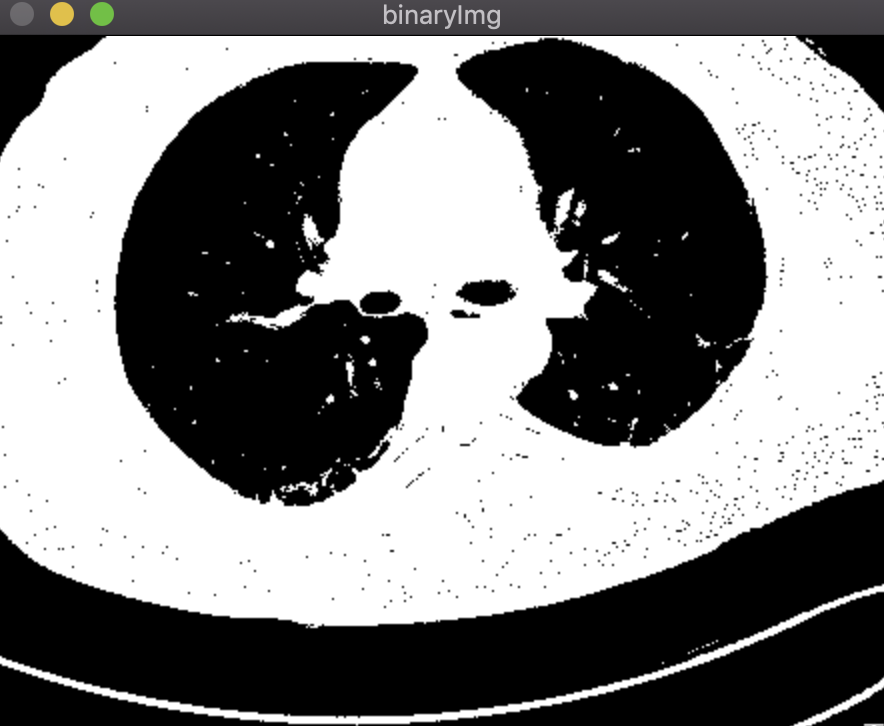

结果:

以下为原图,先转化为灰度图,再转换为二值图。

鼠标先在二值图左肺选取一个种子点,按‘b‘进行分割;然后在二值图右肺选取一个种子点,按‘b‘进行分割,之后做或运算,将两个分割结果合并;最后与灰度图做与运算得到最终分割结果。